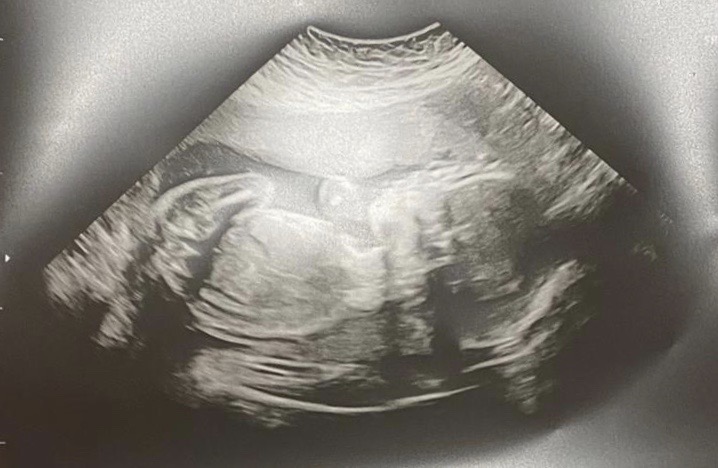

However my tribe don’t always forget me and a video call with some friends is arranged. At long last on the call I ‘met’ my goddaughter’s baby girl, which predictably, made me tear up. She’s the grand daughter of one of my oldest friends and it was a three way call with the new Nanna and my other longest serving friend. I’ve known both these wonderful women since I was 5 years old, and in the season of Corona life goes on. People pass and new babies arrive. The cycle of life is no respecter of Lockdown.